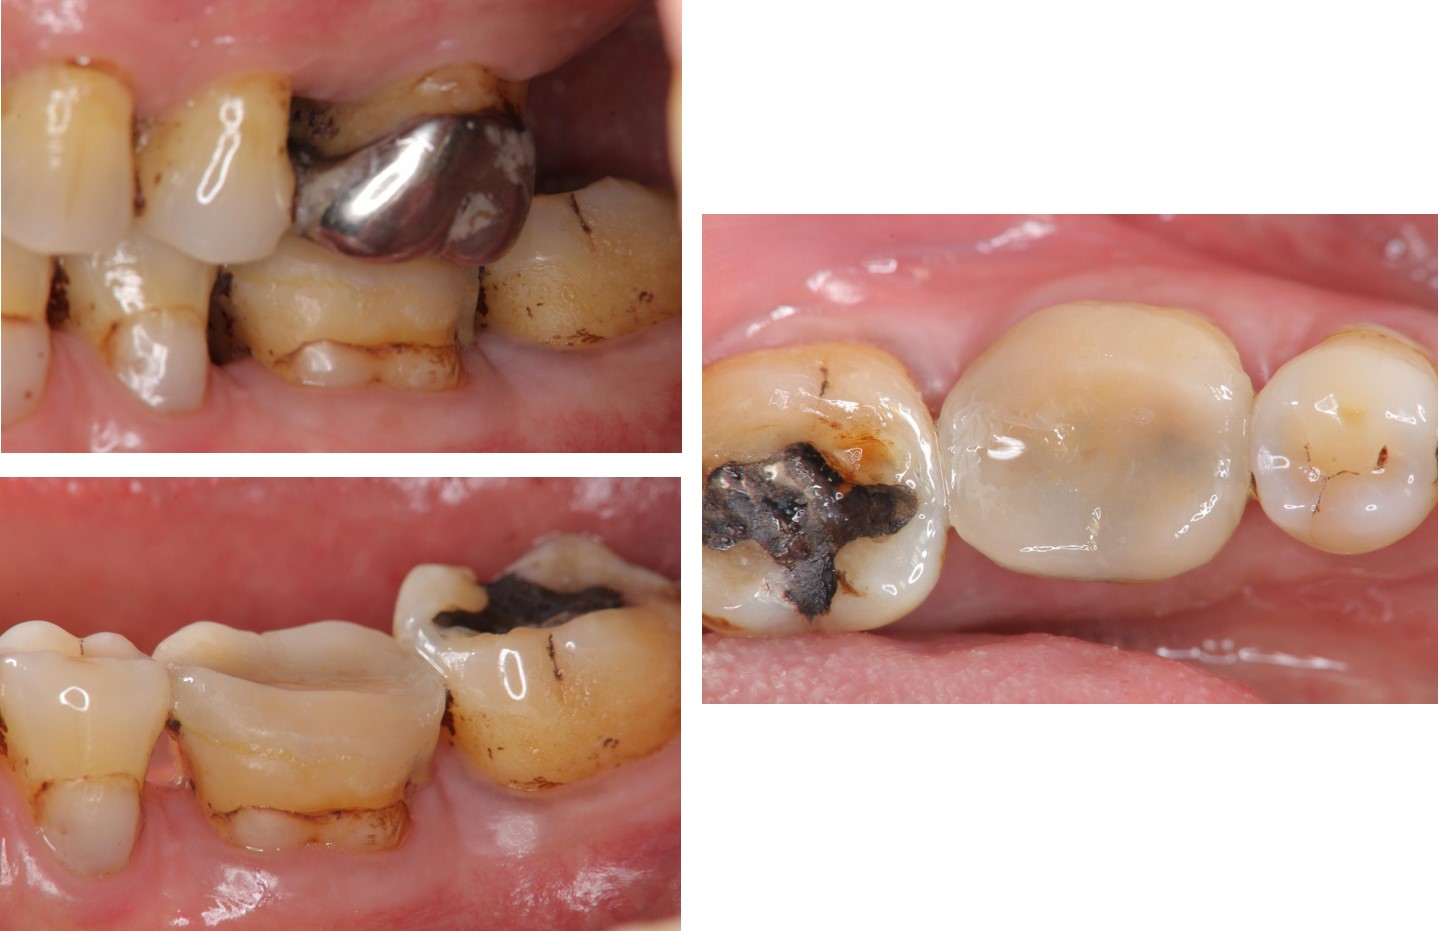

治療前,牙齒嚴重磨耗

治療前,牙髓仍未受侵犯

當磨耗破壞程度大,陶瓷冠塊體是根據蛀牙的窩洞量身訂做,不管是顏色、精密度都是最佳的選擇,因此是非常美觀與持久的填補窩洞材料與技術